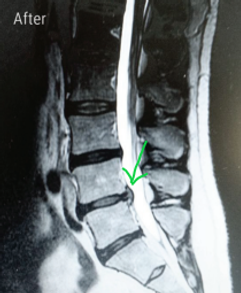

Spinal decompression is a non-surgical, traction-based treatment that gently stretches the spine to relieve pressure on the discs and nerves. It is considered a safe and non-invasive treatment option.

In our clinics, we utilize both KDT decompression and Bac-On-Trac decompression, both are different from traditional traction, as we can target the specific herniated disc and gently distract the vertebras above and below the involved herniated disc. It then releases the pull before the paraspinal muscles have an opportunity to go into spasm. This action causes a drop in pressure in the disc space, thus allowing the herniated disc to be reabsorbed.​